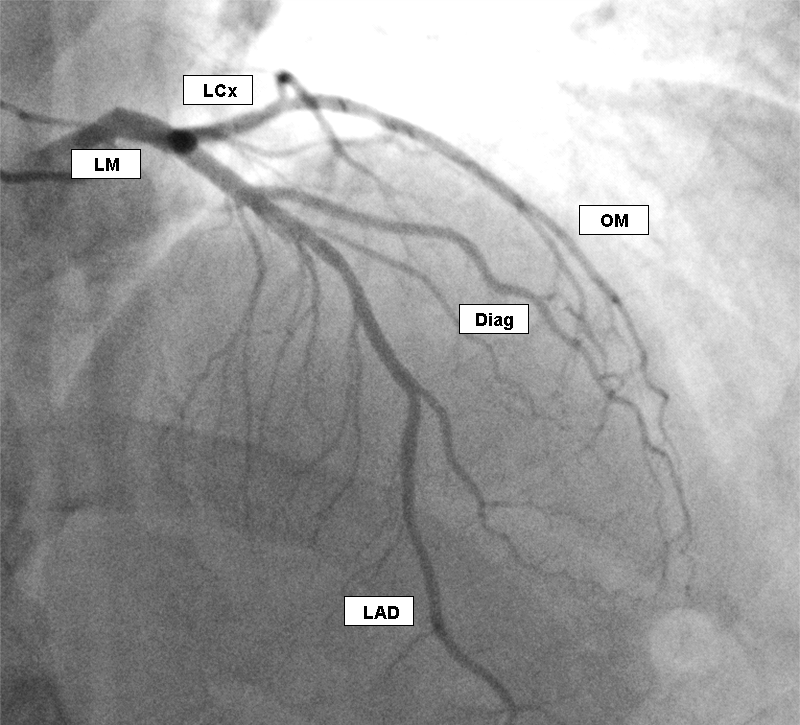

آنژیوگرافی قلب یکی از دقیقترین و مهمترین روشهای تشخیصی در پزشکی قلب و عروق است که برای بررسی وضعیت رگهای کرونر قلب و شناسایی تنگی یا انسداد آنها انجام میشود.

در این روش، از اشعه ایکس به همراه ماده حاجب (کنتراست) استفاده میشود. از آنجایی که رگهای خونی در تصویربرداری معمولی با اشعه ایکس قابل مشاهده نیستند، تزریق ماده حاجب باعث میشود مسیر جریان خون بهوضوح دیده شود و پزشک بتواند هرگونه مشکل در عروق قلب را تشخیص دهد.

ماده حاجب تزریق شده و تصاویر اشعه ایکس ثبت میگردد